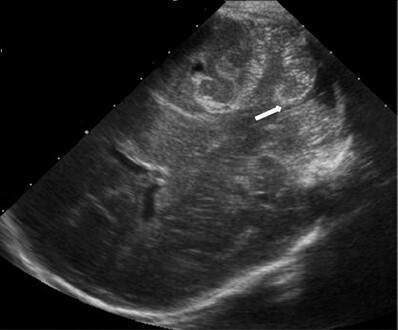

Neonatology Cerebellar Vallecula 2 Image